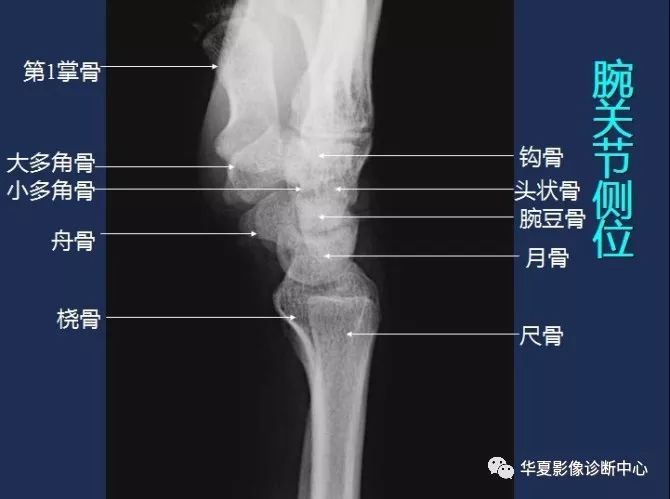

腕关节侧位 医学百科网 | YxBaike.Com